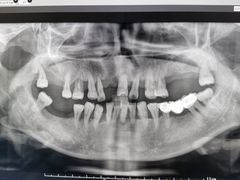

• 牙博士口腔品牌连锁(杨浦店)

• -牙博士口腔品牌连锁(杨浦店)

吴明珍_5071 | 22-02-28